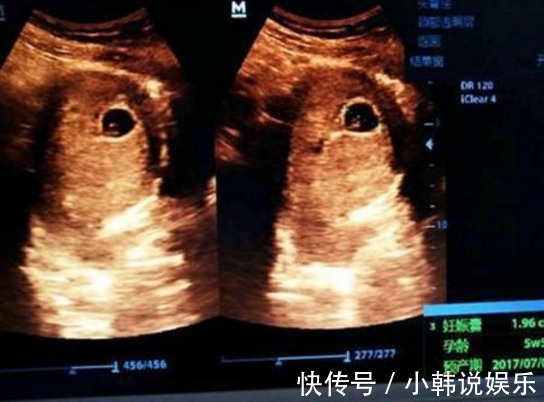

B超单|B超单上的3个“数据”,真幸运,可能怀了个“小棉袄”即将驾到

作为两个孩儿的妈妈,不得不说,在我怀孕过程中最关注的的事情无非就是两个:第一、男孩还是女孩;第二:孩子是否健康。对于一些生二胎的宝妈来说,想知道自己肚子中宝宝的性别,而医院里是有相关规定的,不允许医生私自向准妈妈透露宝宝的性别,那么准妈妈怎样才能知道自己腹中到底怀了个什么呢,其实在预检的B超单上就可以表现出来。

好多人说各种判断不准或者怎样,个人认为:根据个人体质不同会有区别,但是因为怀男孩女孩所产生的不同种激素,会导致每个人反应不同才是更大原因,孕检时,B超单上的3个“数据”,真幸运,可能怀了个“小棉袄”!(1)宝宝的股骨长:妈妈在怀孕的六个月左右的时间内,宝宝的各个器官就已经发育得比较成熟了,因此宝妈在做四维彩超的时候。

B超检查既能对胎盘定位、羊水测量,又能对单胎多胎、胎儿发育情况及有否畸形和葡萄胎等作出早期诊断。就可以看到宝宝的各个器官,当准妈妈拿到B超单时,可以观察宝宝的股骨长,如果宝宝的股骨长比较大的话,那么肚子中怀的很有可能就是一位男宝宝了,相反的话,如果不够长,没有那么大比较偏小的话,那么很有可能就怀的是个“小棉袄”,

(2)宝宝的胎心率:准妈妈怀孕晚期,是很多准妈妈都会做天行健果,而有的准妈妈在做胎心监护的时候,可以通过宝宝的胎心率来反映宝宝的身体健康状况,其实可以通过宝宝的胎心率,也可以明显的感觉出宝宝的情况下,20到160之间属于一个比较正常的,一般来说,彩超的辐射比黑白B超的辐射要大。在孕早期,医生一般选择给孕妇做黑白B超,确定胎儿受孕情况。

到了孕中期,为了能够观测到胎儿的血液流动情况,胎儿是否存在大方面的畸形,及时发现胎儿的异常,才会做彩超。如果在150到160之间的话可能性比较大一些,如果在120到150不是之间的话,那么很有可能怀的就是一位“小棉袄”了。

(3)双顶径:她准妈妈拿到B超单上可以反复观察双流这项数据,就是指的是宝宝头部的宽度,如果准妈妈发现双顶径的数据减去股骨长的数据大于二的话,那么多的小王子的可能性就比较大一些,因为小王子的头部要比小棉袄主的头部大一些,当然这些数据也没有什么百分之百的确定性,只不过是过来人的一些经验总结。孕中期的B超检查,可以面部、神经系统、消化系统、泌尿系统等有无畸形。

孕晚期的B超检查能诊断是否前置胎盘,胎盘成熟度、羊水AFI的多少,决定是否需要终止妊娠等。小编想说不管是男孩还是女孩,我觉得最重要的健康,只要准妈妈的心情美美哒,相信你肯定可以孕育最优秀、最健康的宝宝,希望所有的准妈妈都如愿以偿啊!